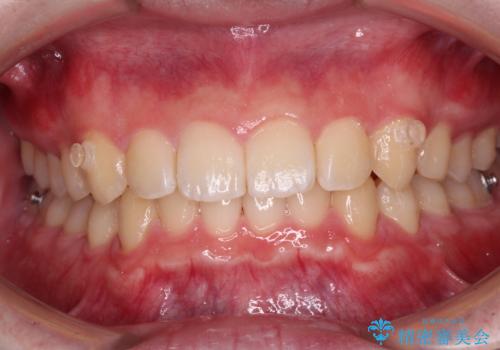

【モニター】斜めに突き出した前歯をインビザラインで改善

- 前方に傾斜した前歯を気にして来院された患者様です。

強く食いしばってしまう癖があり、下顎前歯に押し出されて上顎前歯が前方へ斜めに突き出している状態でした。

IPR(歯と歯の間を削る)を多用して、インビザラインにて矯正治療を行うこととしました。

口元を引っ込めるためのゴムかけを頑張っていただき、満足のいく上顎前歯の傾斜へ改善することができました。